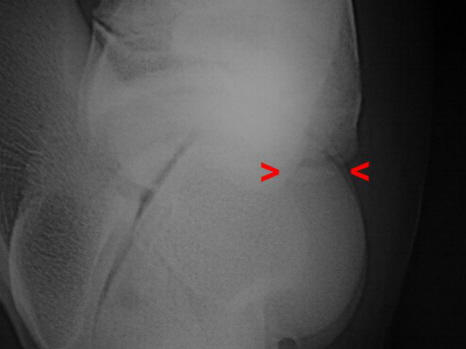

Cip Sprunggelenk